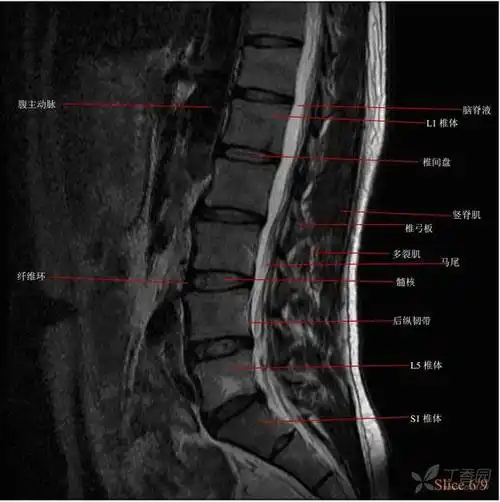

mri平扫图片示明显的腰椎间盘突出(图片来自上海中山医院)